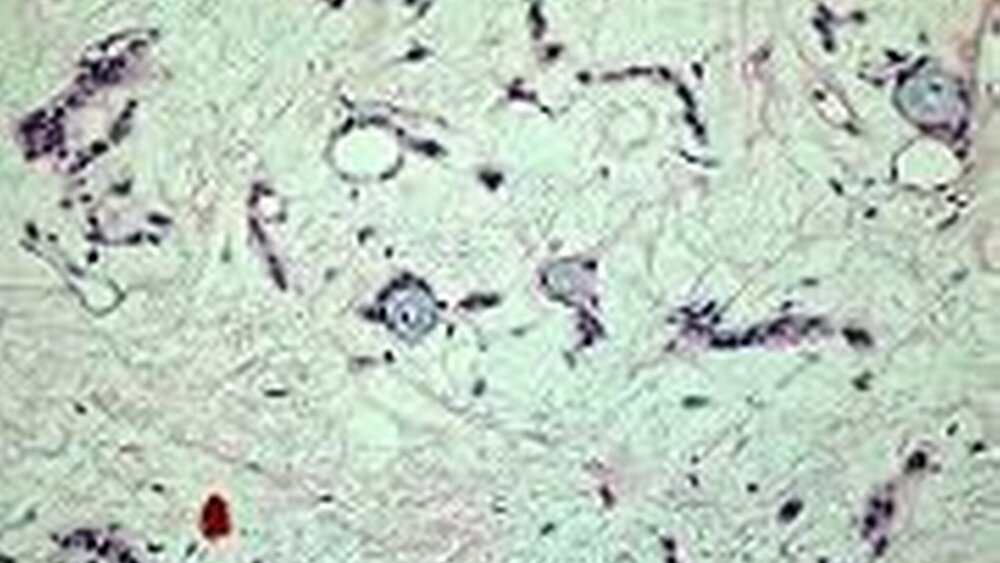

Histologisch ergab sich die abschließende Diagnose eines pleomorphen Adenoms der kleinen Speicheldrüsen. Die Abbildungen 4 a bis c zeigen die histomorphologische Heterogenität eines typischen pleomorphen Adenoms. Drüsenähnliche, tubulär strukturierte Bereiche (Abb. 4a) wechseln mit zellreichen Arealen (Abb. 4b). Daneben finden sich zellarme, stromareiche Bezirke mit vereinzelten drüsenähnlichen Schleim bildenden Zellnestern (Abb. 4c). Die histologischen Bilder entstammen sämtlich dem gleichen Präparat.

Die Problematik einer Diagnose auf der Basis einer nicht repräsentativen Biopsie wird durch die Vordiagnose eines kanalikulären Adenoms deutlich. Offensichtlich war hier zuvor ein Tumoranteil befundet worden, der scheinbar homogen (monomorph) aus tubulären Strukturen aufgebaut schien. Das typische Erscheinungsbild eines solchen kanalikulären (monomorphen) Adenoms entspricht der in Abbildung 4 a dargestellten Morphologie. Erst die Betrachtung des gesamten Tumors führte zur abschließenden Diagnose eines pleomorphen Adenoms.